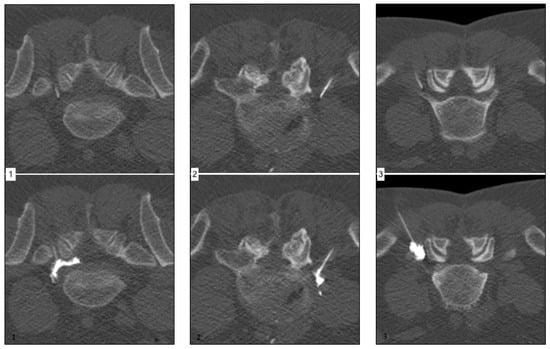

Figure 1 (left) shows a representative case of a 57-year-old male patient suffering from acute onset predominantly radicular LBP of the left-handed side, corresponding to the L5 root dermatome (VAS prior injection: 8) for two weeks. The final needle position was achieved per primam without the need for further corrections. Extensive continuous periradicular and epidural opacification (level 3) was achieved. The patient reported an immediate pain relief (VAS 0), which endured over the six-month period.

Figure 1 (middle) shows a representative case of a 49-year-old male patient suffering from acute onset predominantly radicular LBP of the right-handed side, corresponding to the L5 root dermatome (VAS prior injection: 7) for eight weeks. Needle placement was performed without difficulties. Spatially confined contrast agent dispersion along the nerve root (level 2) was achieved. The patient reported a moderate pain relief (VAS 4) after approximately 8 h, which endured for six weeks only.

Figure 1 (right) shows a representative case of a 58-year-old male patient suffering from acute onset predominantly radicular LBP of the left-handed side, corresponding to the L5 root dermatome (VAS prior injection: 7) for three weeks. Despite unchallenging anatomical circumstances, needle placement was difficult due to anxiety and agitation of the patient. Peripheral contrast agent dispersion without an immediately apparent nerve root contact was achieved. The patient reported no significant pain relief (VAS 6) after 24 h.

Figure 1. Corresponding examples of contrast agent distribution pattern.